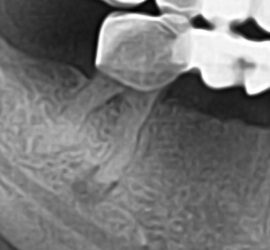

Ретроградный кариес. Кариозный процесс разрушает дентин со стороны пульпы. Наблюдается при наличии интактной, кариозной и пломбированной коронки, а также в случае гангрены пульпы кариозного и травматического происхождения. Со стороны полости пульпы идет процесс распада дентина за счет функции микроорганизмов и протеолитических ферментов. Ретроградный кариес может иметь место при хроническом пролиферативном […]